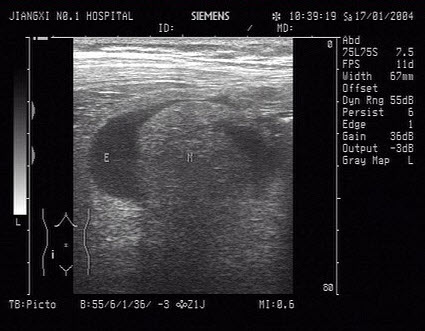

该图为睾丸声像图,最可能的诊断为()